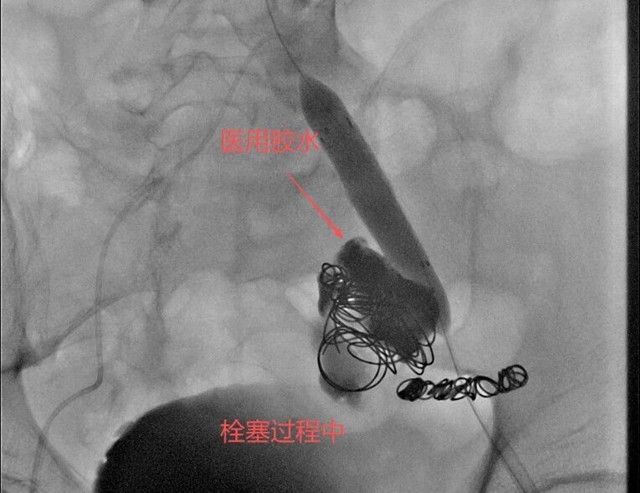

徐燕能博士选择了弹簧圈+医用胶水的复合栓塞技术——这项技术在介入医学界被戏称为“钢筋水泥”结构。“弹簧圈就像钢筋,能够在动脉瘤内形成一个稳定的框架结构;医用胶水则是水泥,填充在弹簧圈形成的框架中,迅速固化形成致密的栓塞体。”

这种组合的优势在于既能快速止血,又能形成长期稳定的栓塞效果,防止动脉瘤再次扩张或破裂。

随着弹簧圈被精准放置到动脉瘤腔内,医用胶水随后注入,两者结合形成了坚固的“钢筋水泥”结构,牢牢封堵了破裂处。